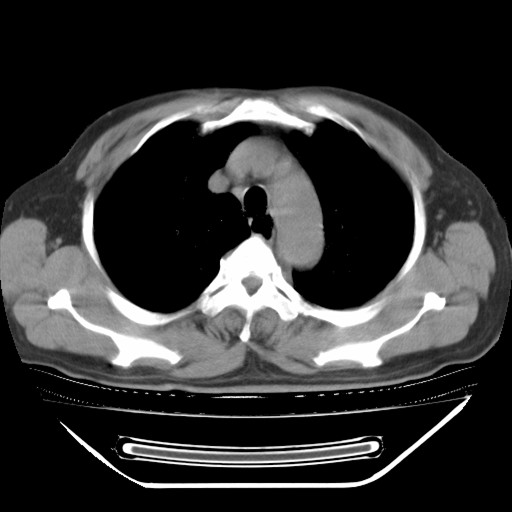

以下是引用hhcckk在2009-5-29 10:34:00的发言:[br]左下肺片絮状边缘模糊影,考虑感染,建议治疗后复查[br]